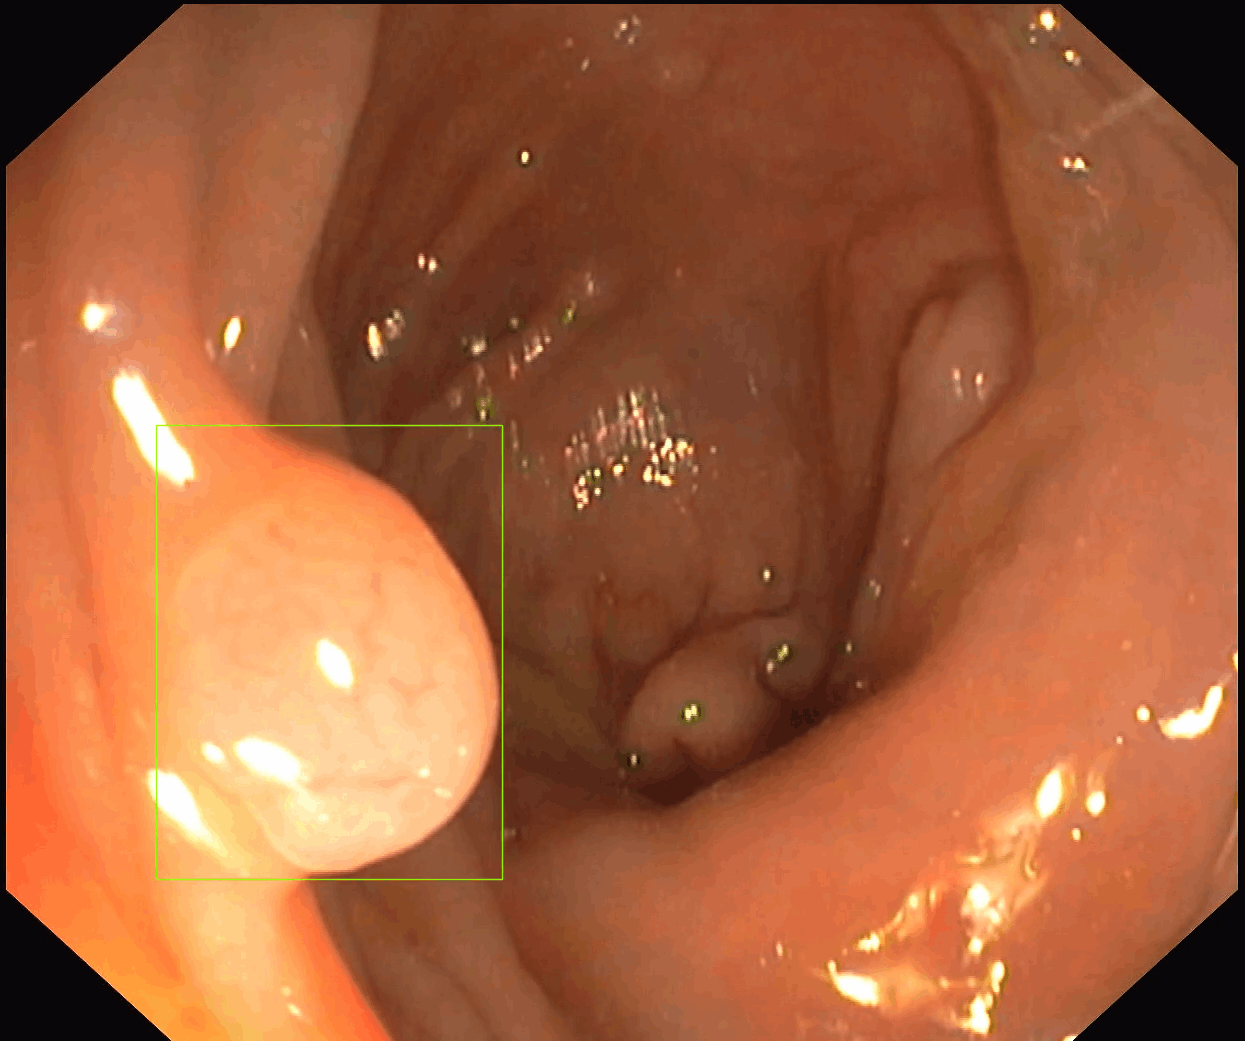

Our first product, SofiOne, is undergoing clinical validation as a decision support tool for the diagnosis of all polyp findings in colonoscopy.